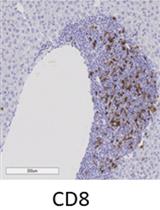

NKG2D is expressed on all NK cells and on subsets of NKT, CD8, CD4 and γδ T cells. NKG2D is activated by NKG2D ligands, a stress-induced family of MHC-I-like proteins. These ligands are upregulated on stressed/infected cells and are not widely expressed on healthy adult tissue. NKG2D ligands have been widely studied as potential targets for immunotherapeutic approaches in cancer and auto-immune diseases such as Systemic Lupus Erythematosus. Here we describe a method for quantifying the expression levels of the Rae-1 NKG2D ligand in the glomeruli of healthy and diseased individuals via a novel algorithm. The MRL mouse was used as a positive control strain as it spontaneously generates a lupus-like phenotype, one of the main effects of which is severe glomerulonephritis. MRL/MpJ mice develop this phenotype spon¬taneously at ~12 months of age, whereas MRL/MpJlpr mice, which have the same genetic background but which generated a spontaneous homozygous mutation in the Fas allele, develop similar but more severe symptoms by ~3-4 months of age (Spada et al., 2015).